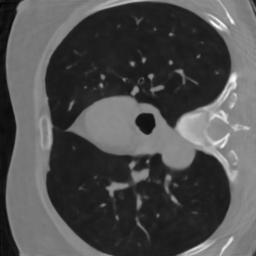

Computerized tomography

We consider parallel beam X-ray computerized tomography. It consists in probing line integrals of an object along a set of parallel lines that may be rotated and shifted. In this application the parameter represents the angles and shift at origin of the lines. The problem becomes blind if the object to image moves during the scan.

4.3.2 Computerized tomography

In this modality, we assume that the distribution of projection angles follows a uniform distribution centered on a vector of regularly spaced angles (see the red lines in first row of Fig. 1) and shift at origin . Hence, we have with and the random shifts are . These perturbations may reflect movements of the patient inside the scanner during the scan.

We trained the network using iterations using the ImageNet database. We initially used the Lung Image Database Consortium [7] database, but realized that it contains many improper slices (high noise, streaking artifacts, little contents…). We evaluated the algorithm on a curated version called LoPoDaP [58], containing less artifacts. The test dataset contains 4096 images.

As the blind inverse problem (5) requires differentiating the operator with respect to its parameters , we cannot use standard GPU-based libraries to compute the Radon transform [76]. We thus resorted to an homemade implementation that relies on a NUFT through the Fourier slice theorem. In order to reduce the important numerical cost and energy consumption of the experiments with CT reconstruction, we downsized the images to .

For CT reconstruction, we considered measurements coming from randomly perturbed versions of the equiangular pattern . The network is an unrolled ADMM ran for iterations. The perturbations belong to the family used for the family training. The perturbation is twice larger than what was observed during the training phase and does not belong to .

6.3.2 Computerized tomography

In this application, a model mismatch might occur due to the motion of a patient in the scanner. Correcting this mismatch is essential. Not accounting for it, can result in severe artifacts including some details loss and blur as can be seen in Fig. 6.

To identify the forward model, we ran the Adam optimizer on the parameters for iterations. In this application, represents the angle of the parallel shots and their shift at origin. All the reconstruction methods are able to significantly reduce the model mismatch, passing from maximal angles shifts of 7 degrees to less that 1 degree. Similarly, the shifts at origin are reduced from more than a pixel to about pixel. The reconstruction performance is significantly improved after estimating the forward model with PSNR increases of dB and more. The neural network trained on a family provides the best reconstruction results on this example.

Similarly to blind MRI, Table 4 shows that the “deep unrolled prior” method consistently provides good estimates of the forward model and significantly improves the reconstruction quality for the CT experiments.